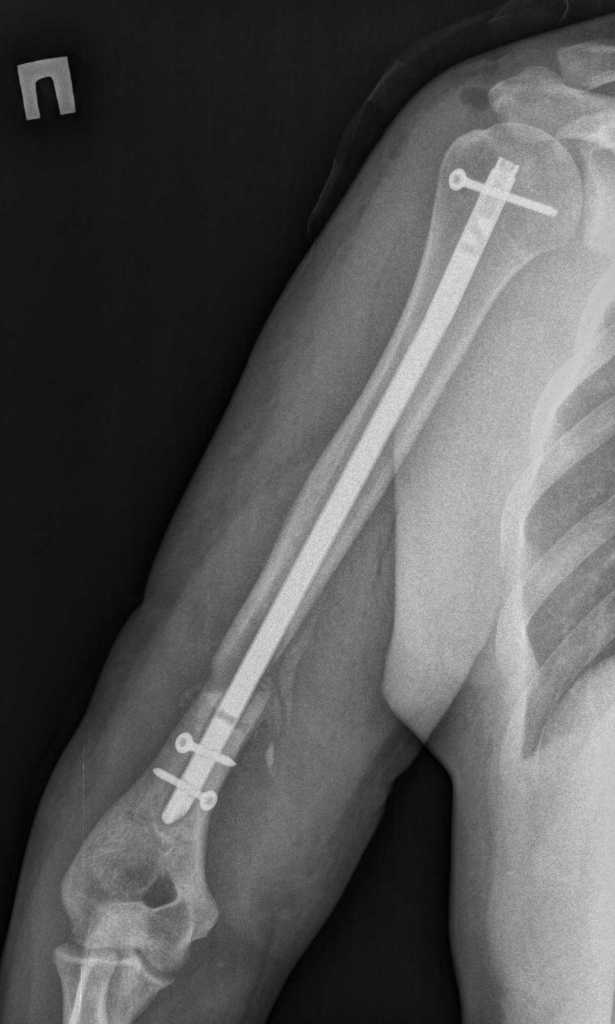

Здравствуйте. Открыто удалили дистальный фрагмент. После рассверливания заштифтовали более массивным штифтом. Спасибо за участие в обсуждении случая.

Имя     : Koval'chuk^A.V.00001.jpg